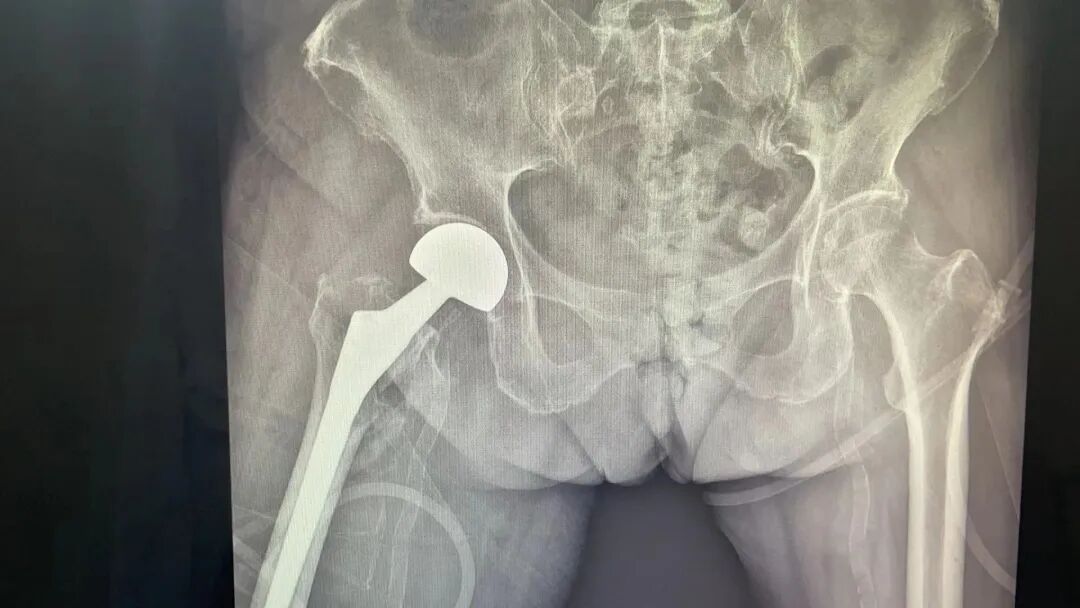

三真骨与关节康复团队为患者实施了右髋关节人工股骨头置换术。

考虑到患者有脑梗死、高血压、糖尿病、冠心病等多重疾病,为确保手术安全和术后康复质量,医院组织了全院大会诊,对付奶奶病情进行充分讨论,并制定了手术康复一体化的治疗方案。在充分做好术前各项准备后,骨与关节康复团队顺利为付奶奶实施了右髋关节人工股骨头置换术。

术后影像学检查显示假体位置良好。